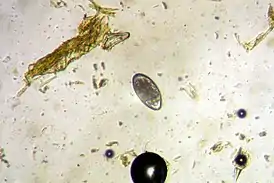

Возбудитель — нематоды из рода Haemonchus. Распространено по всему миру. Гемонхусы достигают 18—35 мм длины. Личинки развиваются во внешней среде.